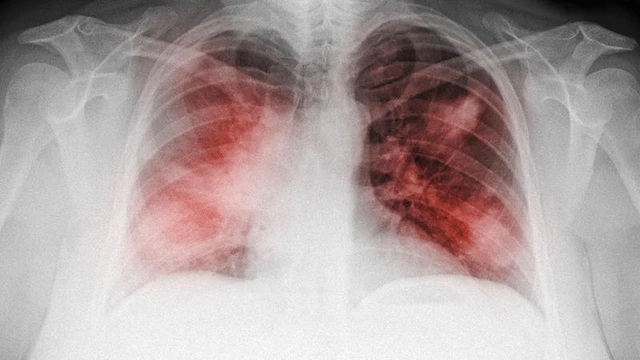

Xơ phổi là một tình trạng y tế nghiêm trọng, xảy ra khi mô phổi bị tổn thương và thay đổi cấu trúc dẫn đến việc mất khả năng cung cấp oxy hiệu quả cho cơ thể. Một trong những phương pháp phổ biến và hiệu quả nhất trong việc phát hiện bệnh là chụp X-quang xơ phổi. Hãy cùng Nhà Thuốc Long Châu tìm hiểu về thông tin này trong bài viết dưới đây.